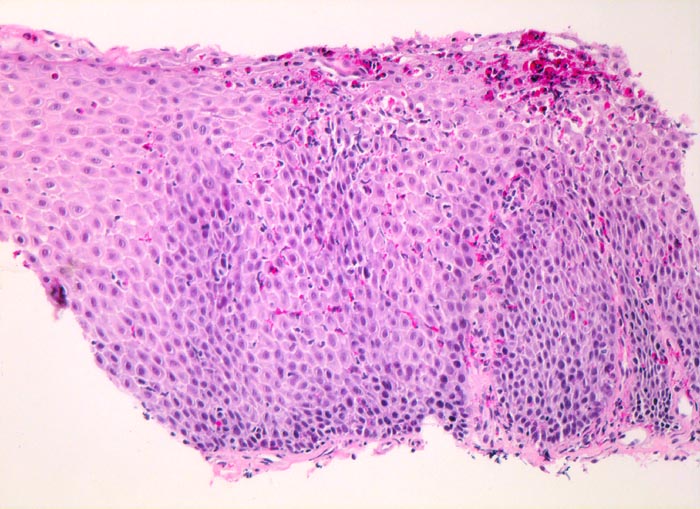

Die Ösophagusschleimhaut zeigt stark verlängerte Papillen, eine Verdickung der Basalzellschicht und ein eindrückliches Infiltrat eosinophiler Granulozyten vor allem im oberen Schleimhautdrittel. Daneben finden sich auch mononukleäre Zellen.

Nach Ausschluss einer Refluxösphagitis (kein Ansprechen auf Refluxtherapie), einer Infektion oder einer Medikamentennebenwirkung ist der vorliegende Befund vereinbar mit einer eosinophilen Ösophagitis. Histologisch finden sich >20 Eosinophile/HPF mit extensiver Degranulation. Die Eosinophilen liegen vor allem in der oberen Epithelhälfte und bilden oberflächliche eosinophile Mikroabszesse. Oberflächliche Abschilferung nekrotischer Keratinozyten gemischt mit Eosinophilen.